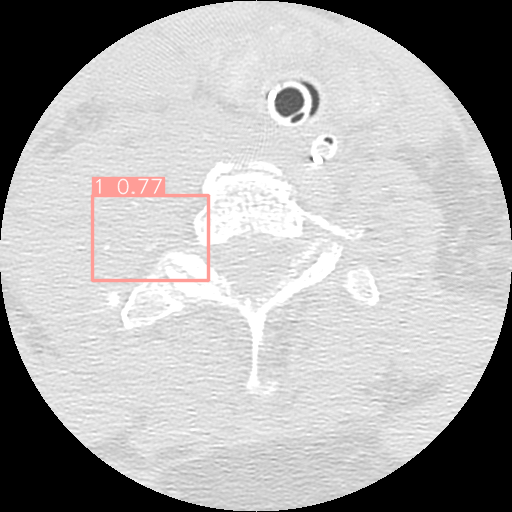

Cervical spine fractures constitute a critical medical emergency, with the potential for lifelong paralysis or even fatality if left untreated or undetected. Over time, these fractures can deteriorate without intervention. To address the lack of research on the practical application of deep learning techniques for the detection of spine fractures, this study leverages a dataset containing both cervical spine fractures and non-fractured computed tomography images. This paper introduces a two-stage pipeline designed to identify the presence of cervical vertebrae in each image slice and pinpoint the location of fractures. In the first stage, a multi-input network, incorporating image and image metadata, is trained. This network is based on the Global Context Vision Transformer, and its performance is benchmarked against popular deep learning image classification model. In the second stage, a YOLOv8 model is trained to detect fractures within the images, and its effectiveness is compared to YOLOv5. The obtained results indicate that the proposed algorithm significantly reduces the workload of radiologists and enhances the accuracy of fracture detection.

2.6 Fracture Detection

The dataset used in this study comprises bounding boxes representing the locations of fractures on vertebrae. To enrich the dataset, an additional set of around one thousand 2D images depicting non-fractured vertebrae has been integrated. The inclusion of these non-fractured samples aims to provide a more comprehensive and balanced representation of the data, facilitating improved model training.

In the pursuit of effective fracture detection, this study leverages the capabilities of two object detection algorithms: YOLOv5 and YOLOv8. These algorithms are to identify fracture occurrences within the images. The choice of utilizing YOLOv5 and YOLOv8 is grounded in their proven effectiveness in object detection tasks, making them suitable candidates for the fracture detection objective at hand.

For fracture detection based on the results, it is clear that the performance of YOLOv8 outperforms YOLOv5. This is a significant improvement, especially considering that YOLOv8 is also faster than YOLOv5. Furthermore, although YOLOv8m has more parameters the mAP50 for YOLOV8s is a bit higher. On the other hand, YOLOv8m has higher mAP50-95. It is evident that YOLOv8s has demonstrated a strong ability to correctly classify images as “Normal" with 194 true positives and only 6 false negatives as presented in Figure 9.